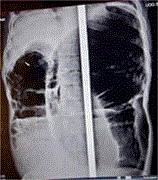

Acute thoracic disc herniation with severe spinal cord compression: a case report

Mario Cahueque and others

Journal of Surgical Case Reports, Volume 2025, Issue 1, January 2025, rjaf001, https://doi.org/10.1093/jscr/rjaf001